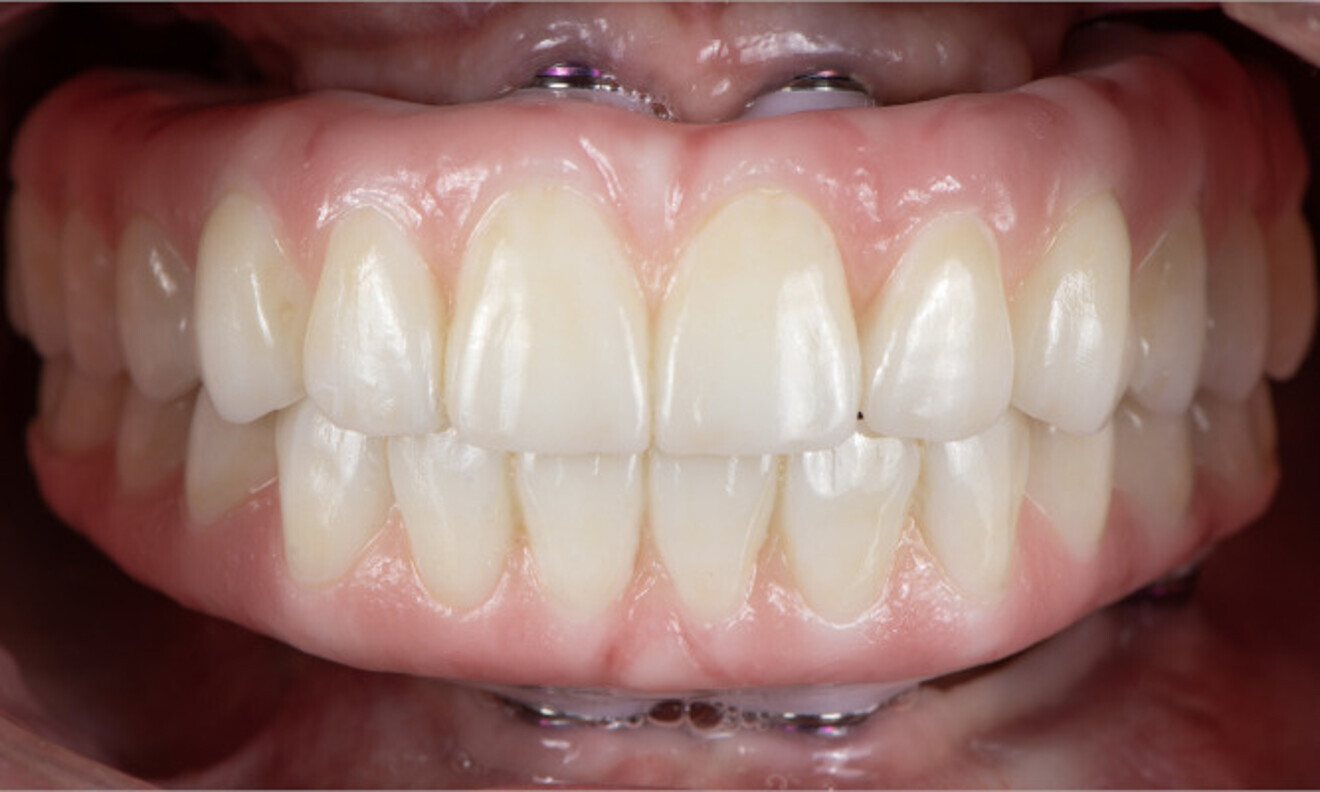

The patient was followed up, and at six months after implant placement, an indirect digitisation of the back-poured master cast was done, allowing for superimposition of the tooth position to the implant position (Fig. 11). The final tooth set-up and occlusal scheme were done digitally to ensure optimised aesthetics and function (Fig. 12). Once everything had been digitally verified, the final zirconia prostheses with layered porcelain gingivae were fabricated (Fig. 13). The occlusion was checked, and the patient was given a 3D-printed occlusal splint to protect the implant-supported prostheses, acting as an absorber and distributor of occlusal forces (Fig. 14). A panoramic radiographic was taken to monitor the health around the dental implants at delivery of the prostheses (Fig. 15). The patient was provided with hygiene instructions and scheduled for regular check-ups to ensure ongoing care and monitoring.

On the same day as extraction surgery, employing the principle of immediacy and without the necessity of guided bone regeneration, an outstanding functional and aesthetic outcome was accomplished with two Straumann BLX implants and two Straumann zygomatic implants in the maxilla and four Straumann BLX implants in the mandible. Six months later, the patient was very pleased with the retention and aesthetics of the final full-arch implant prostheses. The clinical and radiographic evaluation yielded stable and favourable results, indicating positive progress. The prostheses fulfilled the patient’s expectations and needs. She was delighted with the significant change in her smile and in her quality of life (Figs. 16 & 17).